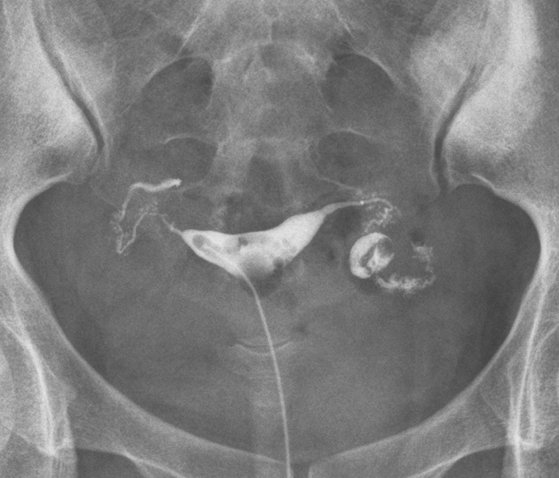

3.png

图3 入院记录,已发生2次宫外孕,做2次腹腔镜